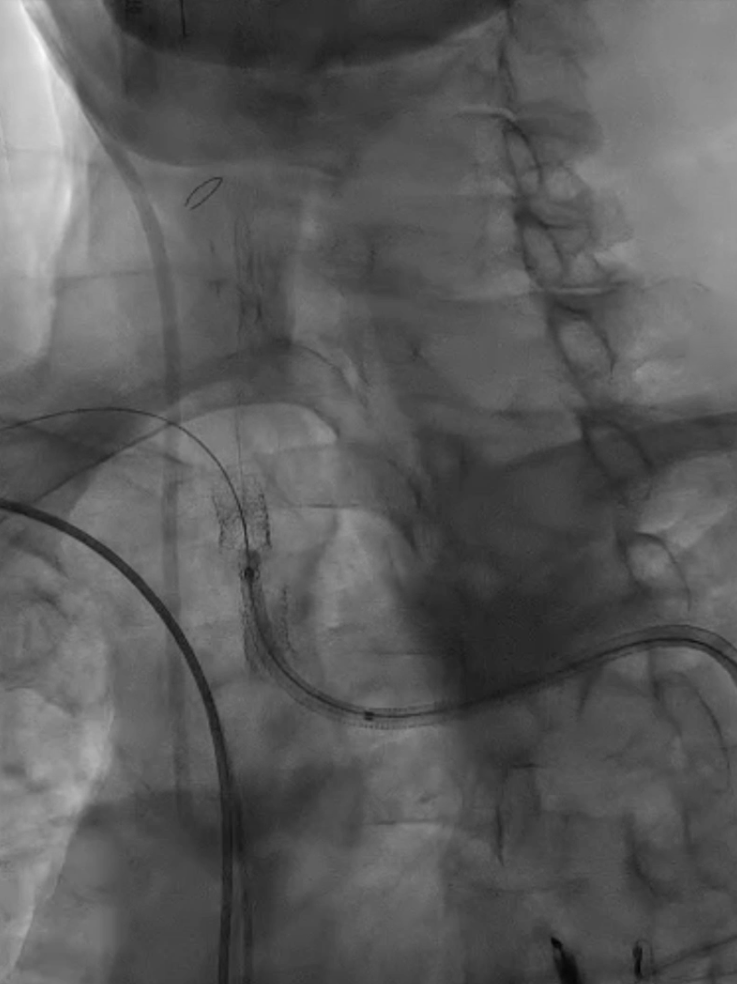

收尾操作:再次以球囊带鞘方式跟进长鞘至支架远端,回收保护伞;最终造影显示支架内血流通畅,右锁骨下动脉、右颈动脉、椎动脉显影良好,椎动脉血流速度较术前明显改善。

长鞘上行困难

回收保护伞

再次球囊带鞘

更进至支架远端

造影支架内通畅

右锁骨下动脉 右侧颈动脉

血流通畅椎动脉显影好